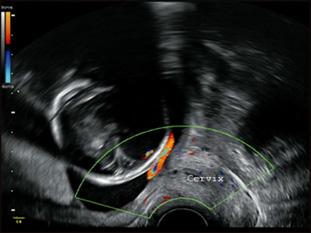

La clínica es un sangrado súbito posterior a la rotura artificial de membrana (amniotomía) durante el trabajo de parto, seguida de una hipoxia fetal (bradicardia fetal o patrón sinusoidal) (ENARM 2019). Se confirma con una ecografía Doppler.